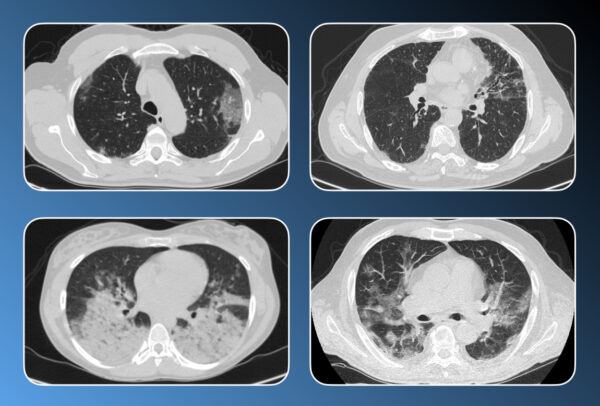

Lung diseases always represent a challenge. The cases of Dr. Macori and Dr. Weerakkody illustrate very well the potential of computed tomography. With didactically well-selected cases the most important diseases are presented.